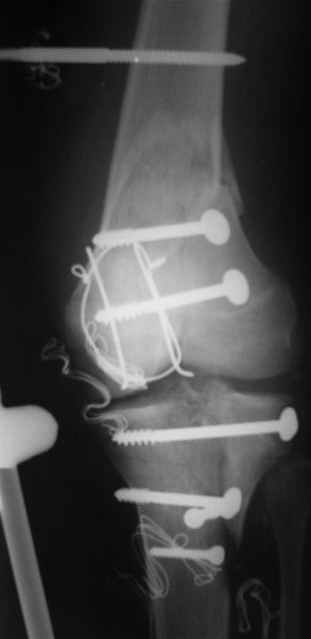

Спасибо за комментарии. Травма тяжелая с проблематичным прогнозом для функции коленного сустава( изначально травма разгибательного аппарата с последующим частичным некрозом собственной связки надколенника и о обнажением рефиксированного фрагмента бугристости большеберцовой кости, дефектом центрального отдела суставной поверхности большеберцовой кости и медиального отдела капсулы сустава).